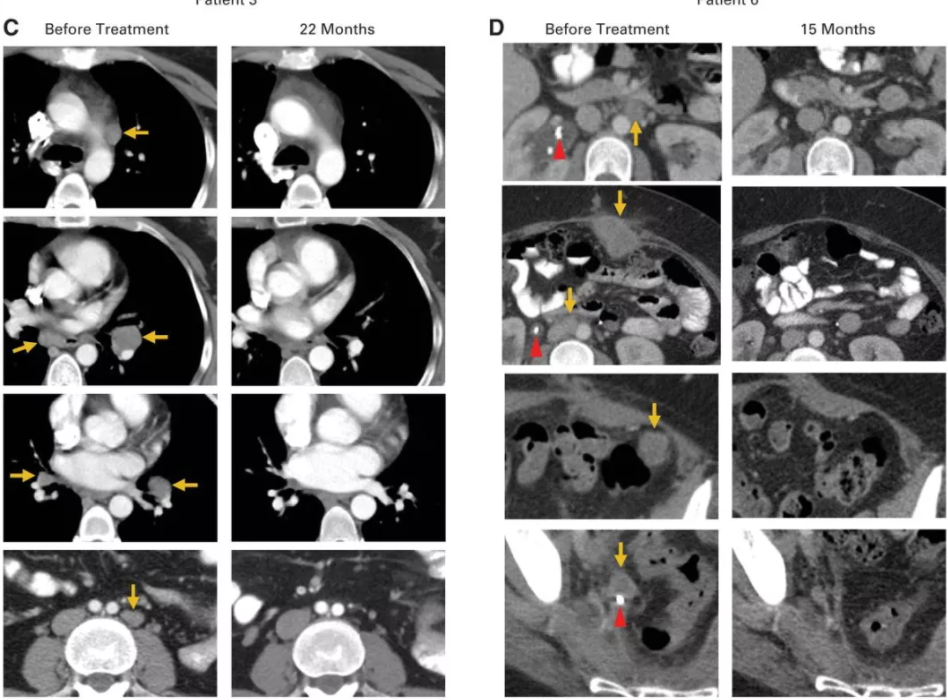

1个月后的第一次扫描,肿瘤已经缩小了50%以上,有些已经完全看不见了;

4个月后,医生看着清晰的扫描结果兴奋的告诉她,“老实说,这是一个奇迹,没有发现任何肿瘤!”这意味着,Aricca所有的肿瘤都消失了。

22 个月后,仍然没有任何癌症的迹象,Aricca已经回到了正常的生活,她和丈夫参加儿子们的球赛,看着他们健康快乐的长大。

Hinrichs博士对Scott说,即使参加试验她可能也活不到一年,因为她全身至少有七个肿瘤在生长:一个在她的肝脏上,另一个像李子一样大小的肿瘤已经可以直接在肚子上看到,结肠附近有一个肿瘤,另一个已经开始阻塞她的一侧输尿管。

一个月后,她的复查结果显示:肿瘤明显缩小了。特别是腹部凸起的肿瘤已经不见了。Scott激动的哭了,因为她一直不敢触碰那个满是肿瘤的地方,现在它却奇迹般的消失了,就好像从来没出现过一样。

治疗两个月后,Scott的复查结果再次震惊了所有人,包括她自己,影像学检查显示,她的体内已经没有任何癌症的迹象。Scott开心的笑了,又哭了,她觉得这是几年来自己第一次畅快的呼吸。

2015年5月,Hinrichs博士第一次将他参与的这项临床试验的初期结果在肿瘤会议上公布,9名患者中的2名-Scott和Aricca Wallace女士的转移性肿瘤全部消失了,完全缓解时间已超过两年。